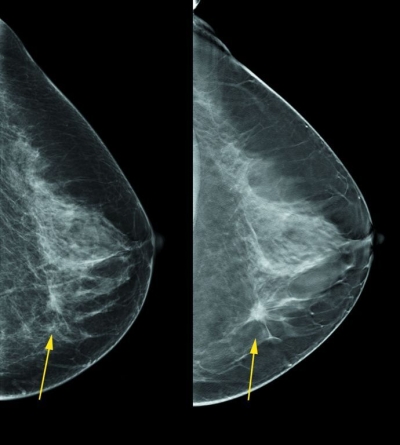

Mamografia (Imagem: Divulgação)

No próximo dia 05 comemora-se o Dia Nacional da Mamografia. Segundo Pesquisa Nacional de Saúde (PNS), realizada pelo Instituto Brasileiro de Geografia e Estatística (IBGE), 40% das mulheres brasileiras, de 50 a 69 anos de idade, não fazem mamografia. Dados do Instituto Nacional do Câncer (INCA) apontam que, no Brasil, as taxas de mortalidade continuam elevadas devido ao diagnóstico tardio.